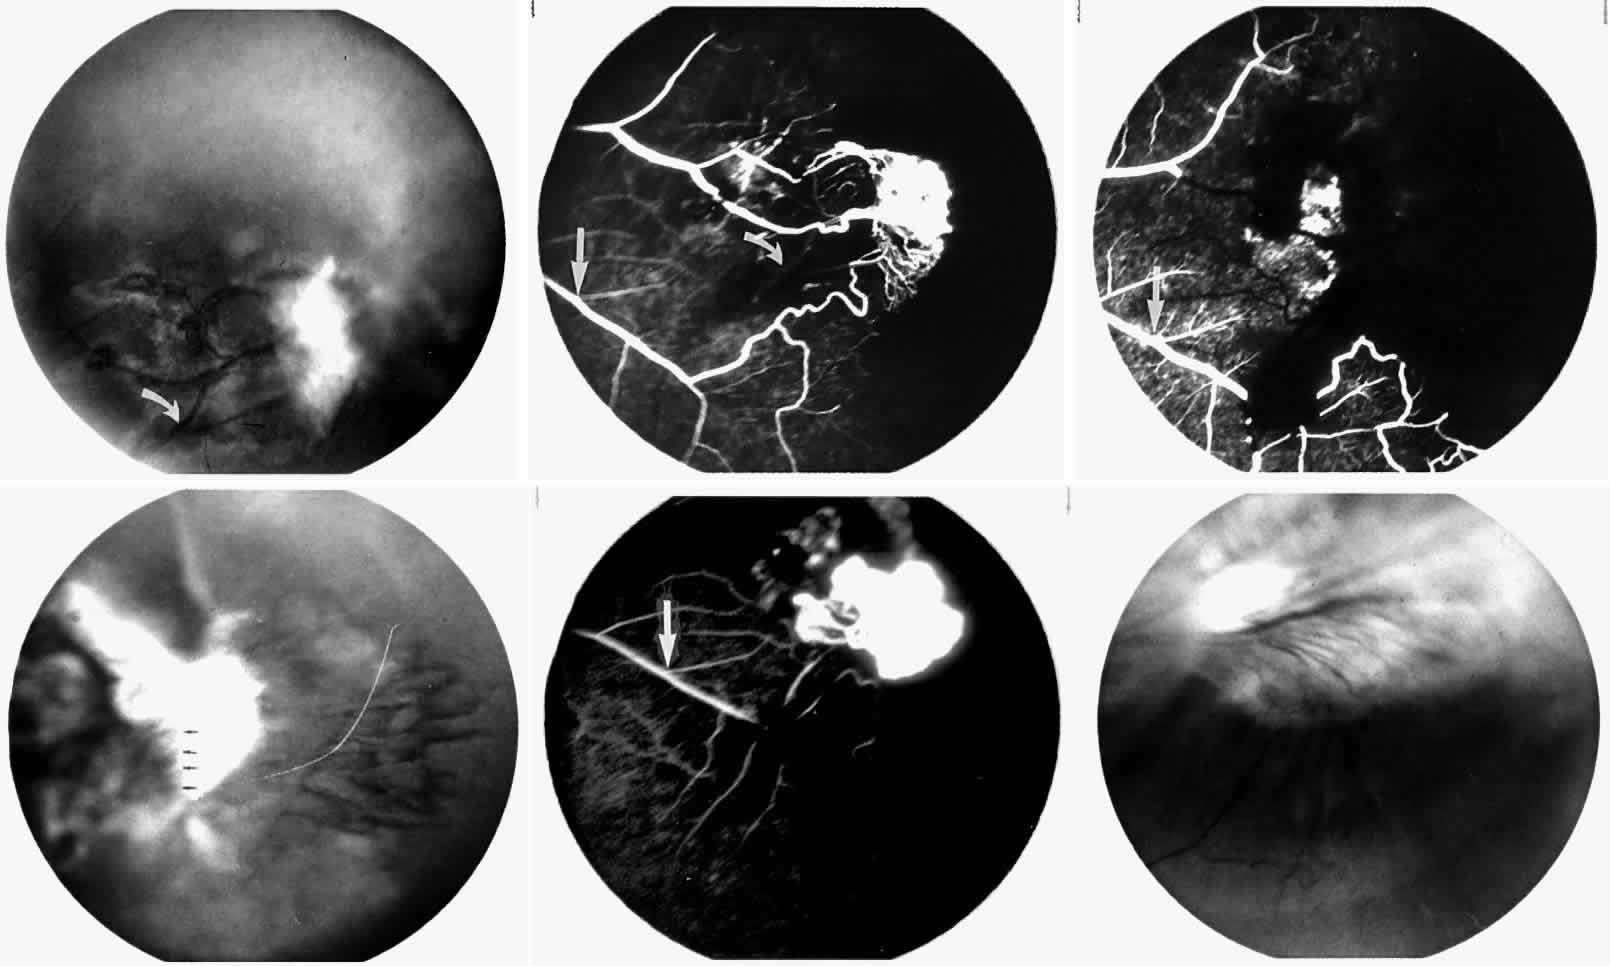

STAGE III: PRERETINAL NEOVASCULARIZATION (PROLIFERATIVE SICKLE RETINOPATHY). “Sea fan”-shaped neovascularization typically develops on the venular side of an arteriolar-venular anastomosis, mimicking the normal development of retinal capillaries (Fig. 24).125 A lowered oxygen tension and angiogenic factors released on the venular side may be the stimulus for neovascular growth.125,126 In most instances, the direction of growth is toward the ora serrata, from the perfused retina toward the nonperfused retina. Presumably, this represents an abortive attempt to revascularize the nonperfused retina, initiated by vasoproliferative factors.

The characteristic neovascular lesions of PSR are called sea fans because they resemble the marine invertebrate Gorgonia flabellum.70 They tend to occur more commonly in the temporal periphery, but they have been reported to occur in the temporal macula in the presence of extensive nonperfusion.130,133 Initially they grow on the surface of the retina, but they often become elevated into the vitreous and adhere to a partially detached posterior hyaloid.114 It may be difficult to visualize small sea fans ophthalmoscopically; however, fluorescein angiography clearly demonstrates leakage of dye into the vitreous (Fig. 25). The feeding arteriole is usually more tortuous than the draining venule (Fig. 26). Early on, the neovascular lesion is fed by a single arteriole and drained by a single venule, but with time, additional arterioles and venules become arborized within the lesion (Fig. 27).129 Growth of the sea fan often occurs circumferentially, rather than radiallyÜmh- 1Ý, toward the ora serrata. Progressive circumferential growth may lead to neovascular lesions extending around the entire periphery. As it matures, a white fibroglial mantle often covers the neovascular tissue (Color Plate 2B).

|

|

PSR is associated with the severe vision-threatening sequelae of sickle cell disease: vitreous hemorrhage (stage IV) and retinal detachment (stage V). These stages are believed to result from transudation of blood components into the vitreous through the incompetent neovascular tissue (Fig. 28). Vitreous fluorophotometry has quantified the leakage from the peripheral neovascularization.134 This leads to premature syneresis and collapse of the vitreous, inducing tractional forces on the retina that lead to vitreous hemorrhage, retinal tears, and tractional and rhegmatogenous retinal detachment. In rare cases, an exudative detachment may occur.

|